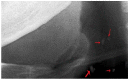

Background: This study sought to determine the prevalence of carotid artery calcifications (CACs) and pulp stones detected on panoramic radiographs (PRs) and ascertain their correlation.

Results: The prevalence of CACs on PRs was 2.0%; the prevalence of pulp stones was 4.6%. There was no statistical relationship between pulp stones and CACs (p = 0.714). Older patients exhibited a significantly higher prevalence of CACs than younger patients (p < 0.001); pulp stones were statistically more prevalent in younger patients than older patients (p = 0.001). There were no significant differences between male and females in terms of the prevalence of either CACs or pulp stones (p = 0.087 and p = 0.278, respectively).

Conclusions: Dentists should be trained to detect CACs on PRs belonging to patients older than 40 to exclude the presence of CACs. Moreover, pulp stones do not function as a diagnostic marker for CACs.